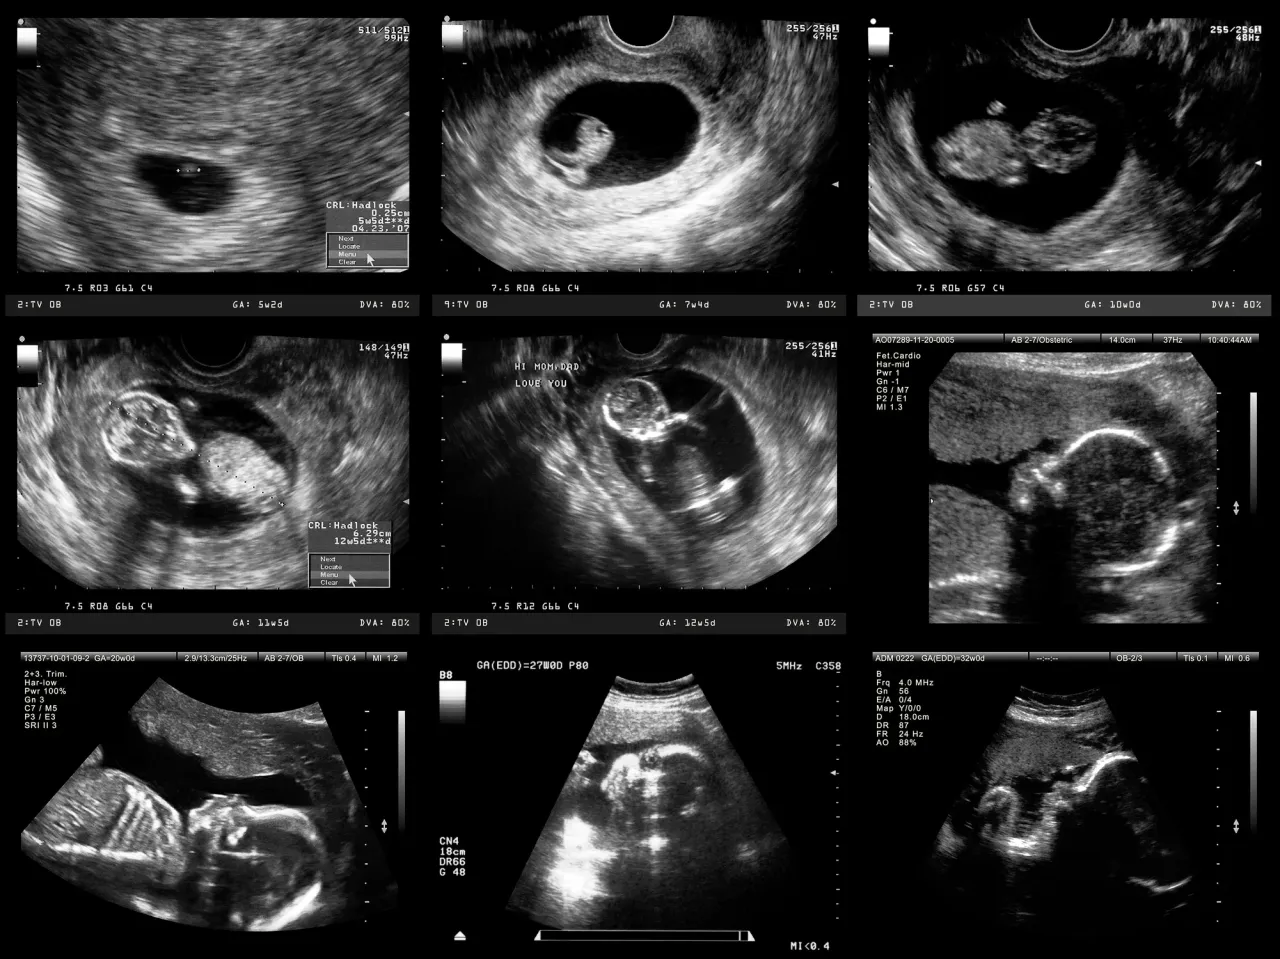

Program badań prenatalnych NFZ koncentruje się na diagnostyce nieinwazyjnej, która pozwala ocenić ryzyko wystąpienia wad genetycznych i rozwojowych płodu bez ingerencji w środowisko wewnątrzmaciczne. Przyjrzyjmy się szczegółowo, co dokładnie jest refundowane w poszczególnych trymestrach ciąży.

Pakiet na I trymestr (11-14 tydzień): USG genetyczne i test PAPP-A.

Pierwszy trymestr to kluczowy czas na wykonanie wstępnych badań przesiewowych. W ramach programu NFZ, między 11. a 14. tygodniem ciąży, przysługuje Ci pakiet składający się z dwóch głównych elementów:

- USG "genetyczne": To szczegółowe badanie ultrasonograficzne, którego celem jest ocena anatomii płodu oraz poszukiwanie tzw. markerów wad genetycznych.

- Badania biochemiczne z krwi matki (tzw. test PAPP-A): Jest to badanie laboratoryjne, które uzupełnia obraz uzyskany z USG.

Połączenie tych dwóch metod, znane jako test złożony (ang. combined test), znacząco zwiększa czułość wykrywania najczęstszych aberracji chromosomowych.

Co ocenia lekarz podczas USG genetycznego i dlaczego jest tak ważne?

USG genetyczne, często nazywane również USG I trymestru, to nie jest zwykłe USG. Lekarz podczas tego badania bardzo precyzyjnie ocenia rozwój płodu, zwracając uwagę na szereg parametrów, które mogą wskazywać na podwyższone ryzyko wad. Do najważniejszych z nich należą:

- Przezierność karkowa (NT nuchal translucency): Pomiar grubości płynu pod skórą na karku płodu. Zwiększona przezierność jest jednym z najważniejszych markerów zespołu Downa i innych wad.

- Obecność kości nosowej: Brak lub niedorozwój kości nosowej również jest silnym markerem wad genetycznych.

- Ocena przepływu krwi w przewodzie żylnym i zastawce trójdzielnej serca.

- Wczesna ocena podstawowych struktur anatomicznych płodu, takich jak mózg, serce, żołądek, pęcherz moczowy, kończyny.

To badanie jest niezwykle ważne, ponieważ pozwala na wczesne wykrycie potencjalnych problemów i ocenę ryzyka wystąpienia wad genetycznych. Wczesna informacja daje czas na dalszą diagnostykę i świadome podejmowanie decyzji.

Pakiet na II trymestr (18-22 tydzień): Czas na USG połówkowe.

Kolejnym kluczowym badaniem w ramach programu NFZ jest USG "połówkowe", wykonywane w drugim trymestrze ciąży, zazwyczaj między 18. a 22. tygodniem. To badanie ma na celu bardzo szczegółową ocenę anatomii płodu i jest niezwykle ważne dla wykrycia ewentualnych wad strukturalnych, które mogły nie być widoczne w I trymestrze.

Co sprawdza USG połówkowe i dlaczego nie można go pominąć?

USG połówkowe to jedno z najważniejszych badań w całej ciąży. Lekarz podczas tego badania poświęca dużo czasu na szczegółową ocenę wszystkich narządów i układów płodu. Sprawdza m.in.: